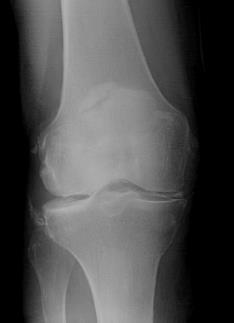

Przedstawiony poniżej obraz rentgenowski stawu kolanowego u chorego po urazie skrętnym bez zaburzeń stabilności w płaszczyźnie czołowej i strzałko- wej oraz ruchomości biernej i czynnej kolana oraz bez balotowania rzepki jest wskazaniem do: